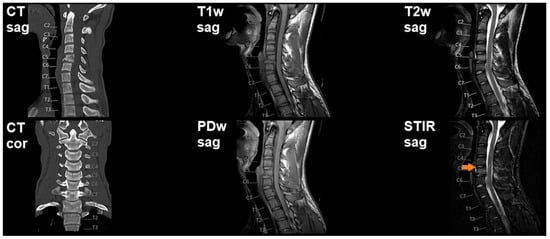

3.2. Imaging and Intraoperative Findings